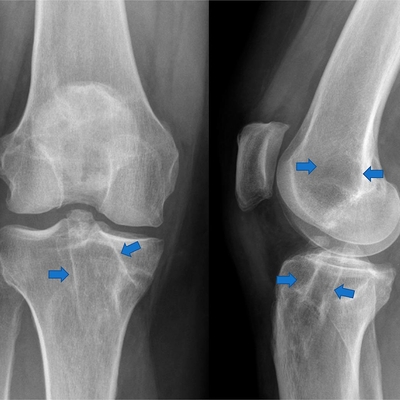

Click on an image below to view more info.